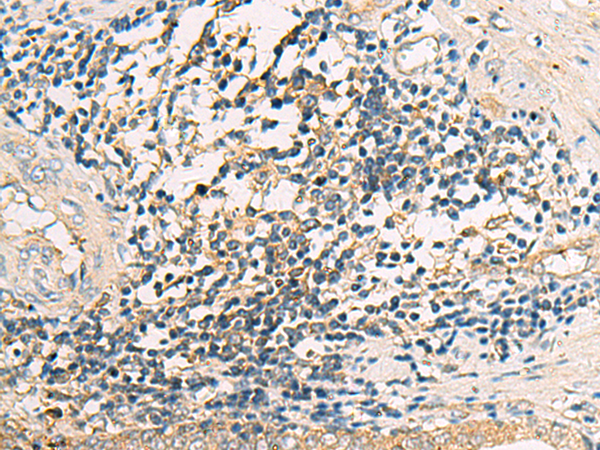

IHC positive control: |

Human prostate cancer |

IHC Recommend dilution: |

25-50 |